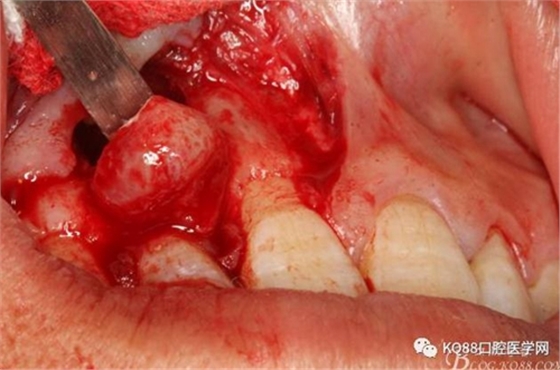

圖8.從垂直切口和水平切口的連接處翻瓣。發(fā)現(xiàn)11和12之間的骨壁有缺損。

圖9.翻開(kāi)角形瓣后,有骨壁缺損,囊壁有穿孔,這就是溢膿的竇道出口。

圖10。用骨膜剝離器沿著骨壁、緩慢逐漸剝離囊壁。